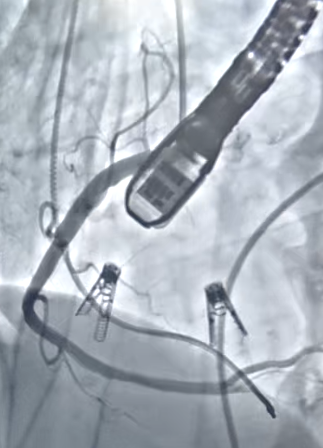

針對吳女士的病情,傳統(tǒng)藥物治療效果有限,而外科開胸手術(shù)進行三尖瓣修復(fù)或置換,對于她這樣高齡、心功能差、合并癥多的患者來說,創(chuàng)傷巨大,手術(shù)風(fēng)險極高,幾乎難以承受。為此,上海市東方醫(yī)院南通瑞慈醫(yī)院王沖主任團隊聯(lián)合心血管內(nèi)科、重癥醫(yī)學(xué)科、麻醉科等多學(xué)科專家進行了深入細致的術(shù)前討論,最終決定采用國際前沿的微創(chuàng)介入技術(shù)——經(jīng)導(dǎo)管三尖瓣修復(fù)術(shù),聯(lián)合心臟起搏器植入,同期解決吳女士的問題。 手術(shù)選用國內(nèi)最新獲批的創(chuàng)新型器械——K-Clip?經(jīng)導(dǎo)管三尖瓣夾合技術(shù),該技術(shù)無需開胸、無需體外循環(huán),僅通過血管穿刺,在超聲和X線引導(dǎo)下,即可將特制的“瓣環(huán)夾”精準(zhǔn)植入擴大的三尖瓣瓣環(huán)處,從外部縮小瓣環(huán)周長,從而有效減少反流,具有創(chuàng)傷小、恢復(fù)快、安全性高的顯著優(yōu)勢。 03 全國首批K-Clip?植入,精準(zhǔn)修復(fù)心臟閥門 手術(shù)在雜交手術(shù)室開展,首先由心內(nèi)科崔勤主任團隊給患者安裝永久起搏器,使患者的心律趨于穩(wěn)定。隨后,在上海市東方醫(yī)院施盛主任的指導(dǎo)下,王沖主任團隊首先在患者右側(cè)大腿根部和頸部的血管建立了幾個比圓珠筆芯還細的通道。為了確保萬無一失,還在心臟的供血血管(右冠狀動脈)里預(yù)先放置了一根保護導(dǎo)絲,以防后續(xù)操作對其產(chǎn)生影響。 △施盛主任與心臟血管外科王沖主任團隊術(shù)中 手術(shù)過程中,施盛主任和王沖主任通過精準(zhǔn)錨定與夾合,將K-Clip?輸送系統(tǒng)經(jīng)頸靜脈精準(zhǔn)送至擴大的三尖瓣環(huán)目標(biāo)位置。通過造影確認(rèn)心臟供血血管安然無恙。術(shù)后即刻的超聲顯示,兩個“小夾子”位置完美,牢牢地將擴大的瓣環(huán)“勒緊”。整個手術(shù)過程如同在心臟內(nèi)部進行了一場精細的“微雕”,出血極少,創(chuàng)傷微小。 △術(shù)中造影 目前,吳女士已恢復(fù)良好并順利出院。此次全國首批K-Clip?植入手術(shù)的成功開展,是上海市東方醫(yī)院南通瑞慈醫(yī)院在結(jié)構(gòu)性心臟病介入治療領(lǐng)域的重大突破,具有里程碑式的意義。 這標(biāo)志著上海市東方醫(yī)院南通瑞慈醫(yī)院心臟血管外科已熟練掌握了國際主流的三尖瓣介入修復(fù)技術(shù),針對復(fù)雜高?;颊?,創(chuàng)造性采用“起搏器植入+K-Clip修復(fù)”的“一站式”復(fù)合手術(shù)方案,實現(xiàn)了心率管理與結(jié)構(gòu)修復(fù)的雙重目標(biāo),最大化患者獲益。同時為那些無法耐受傳統(tǒng)開胸手術(shù)的高齡、高危、重癥心臟瓣膜病患者,提供了一種安全、有效的治療新選擇,顯著改善了其生存質(zhì)量與預(yù)后。